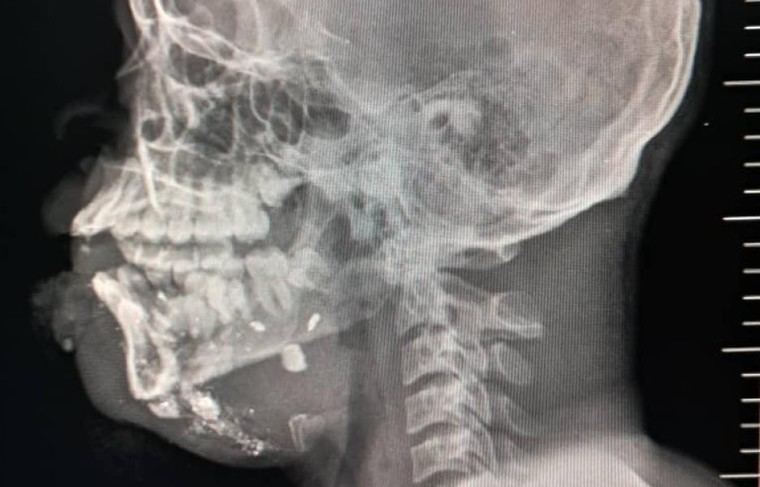

El 20 de septiembre, un ataque con drones en Cité Soleil dejó varios heridos que fueron atendidos en el hospital de MSF en Drouillard. Entre ellos se encontraban dos hombres fallecidos a su llegada y varios otros que no sobrevivieron a sus heridas. Esta violencia es parte de un conflicto territorial donde la población civil queda atrapada entre amenazas constantes.